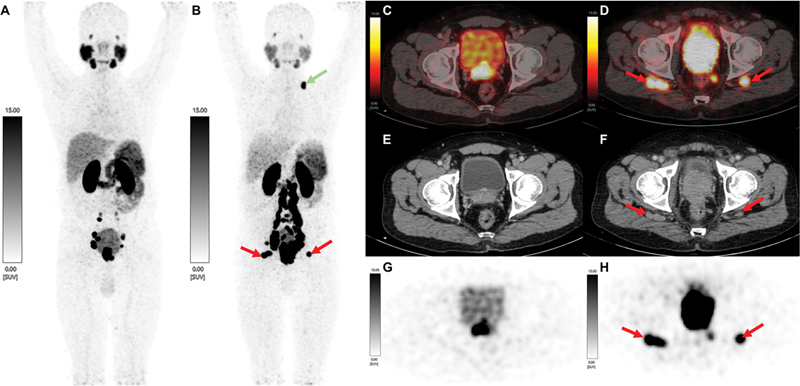

An unusual and unique case of prostate adenocarcinoma with involvement of bilateral inferior gluteal lymph nodes is reported. The patient was a 42-year-old male, with conventional prostatic adenocarcinoma (Gleason score: 5 + 4 = 9), who, during disease progression with rising serum prostate specific antigen levels following medical androgen deprivation therapy, demonstrated new prostate-specific membrane antigen expressing metastatic intermuscular deposits in the bilateral gluteal region, subsequently proven to be bilateral inferior gluteal nodal metastasis. A therapeutic implication to this may be that these nodes usually fall beyond the range covered by the therapeutic radiation field coverage where external radiotherapy is the advocated modality of choice and are not easily reachable through standard surgical procedures. As a result, they could have an impact on the way patients are clinically treated and on their prognosis.

报告了一例不寻常且独特的双侧臀下淋巴结受累的前列腺腺癌病例。患者是一名 42 岁的男性,患有传统的前列腺腺癌(格里森评分:5 + 4 = 9),在接受药物雄激素剥夺治疗后,随着病情的发展,血清前列腺特异性抗原水平不断升高,在双侧臀部区域出现了新的前列腺特异性膜抗原表达的转移性肌间沉积物,随后被证实为双侧臀下淋巴结转移。其治疗意义可能在于,这些结节通常位于治疗放射野覆盖范围之外,而外放射治疗是首选的治疗方式,并且不易通过标准外科手术到达。因此,它们可能会对患者的临床治疗方式和预后产生影响。